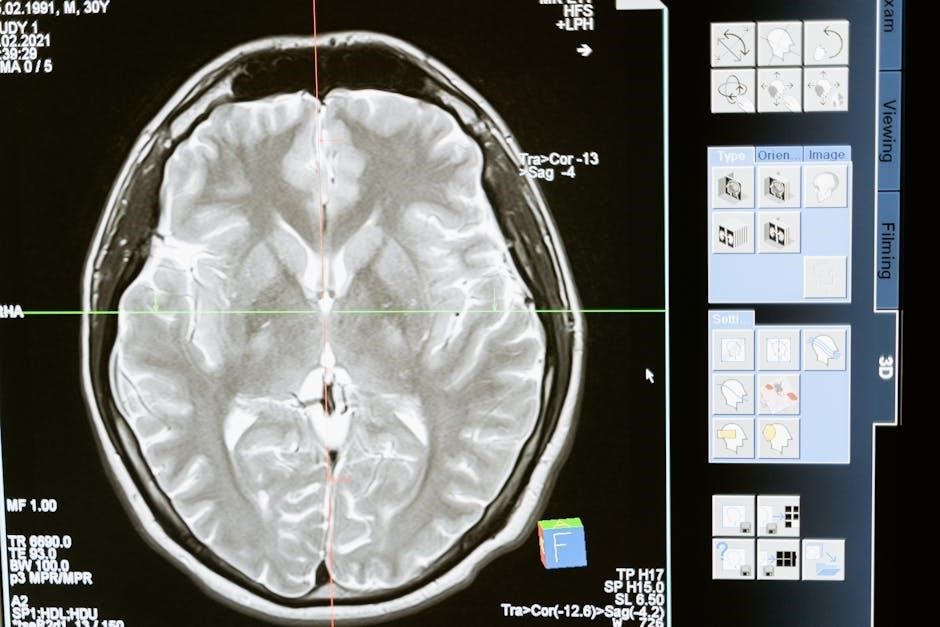

The Dexamethasone Suppression Test (DST) assesses the hypothalamic-pituitary-adrenal (HPA) axis function‚ crucial for cortisol regulation. Obtaining clear dexamethasone suppression test instructions in PDF format is paramount for successful execution. This test utilizes dexamethasone‚ a synthetic glucocorticoid‚ to determine if the body appropriately suppresses cortisol production. A normal HPA axis will reduce cortisol output in response to dexamethasone.

The primary purpose of the Dexamethasone Suppression Test (DST) is to evaluate the body’s cortisol production and identify abnormalities in the hypothalamic-pituitary-adrenal (HPA) axis. Accessing dexamethasone suppression test instructions in PDF format clarifies the test’s role in diagnosing conditions characterized by excessive cortisol. Specifically‚ it helps detect Cushing’s syndrome and differentiate its causes.

PDF guides detail how the test determines if the pituitary gland is responding appropriately to dexamethasone‚ a synthetic cortisol. A failure to suppress cortisol levels suggests a problem within the HPA axis. These PDF resources are essential for healthcare professionals to accurately interpret results and guide patient management‚ ensuring appropriate treatment strategies are implemented.

Cushing’s syndrome‚ stemming from prolonged hypercortisolism‚ is a key condition assessed using the Dexamethasone Suppression Test‚ with detailed guidance available in PDF instructions. These dexamethasone suppression test instructions in PDF explain how the test reveals the body’s ability to suppress cortisol production when given dexamethasone – a synthetic glucocorticoid. Failure to suppress indicates an issue with cortisol regulation.

PDF resources highlight the link between untreated Cushing’s and severe complications like heart attacks‚ strokes‚ and type 2 diabetes. The DST‚ as outlined in PDF protocols‚ helps pinpoint the source of excess cortisol‚ guiding treatment strategies. Understanding these instructions is vital for accurate diagnosis and patient care.